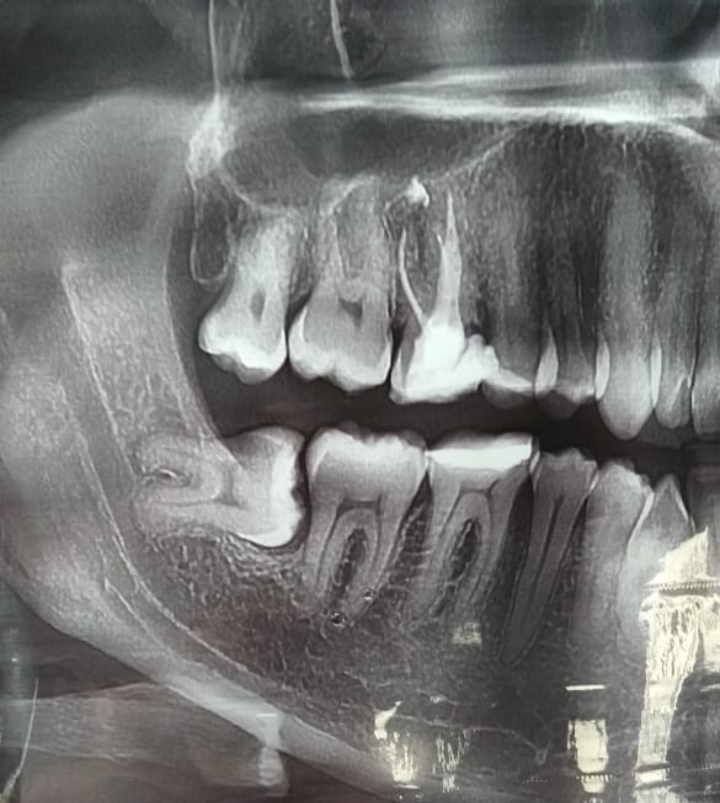

Правильный диагноз можно поставить только с помощью 3D-сканирования области с зубом мудрости. На рентгенографии врач сможет увидеть точное место локализации воспаления. Кроме этого, итог рентгенологического исследования помогает правильно подобрать методику лечения или принять решение о необходимости хирургического вмешательства.

• проведение рентгенографии и получение её результата;